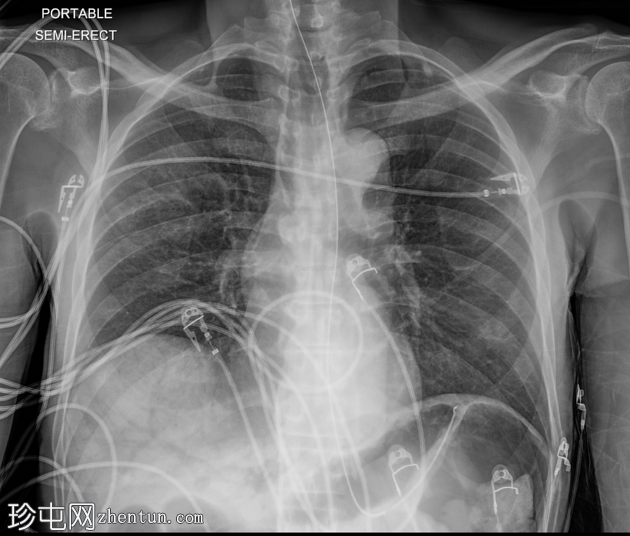

2.png

正位片